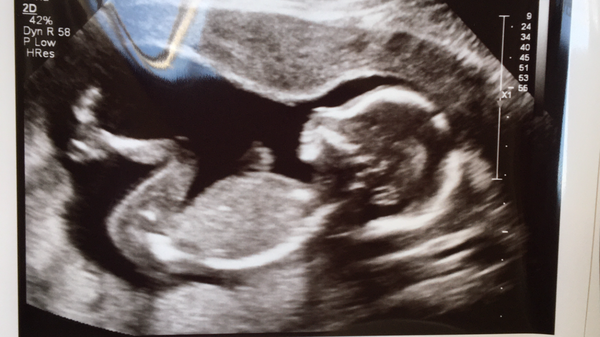

chubbyhotchoc · 08/07/2020 18:52

@alphabetti welcome. This is mine and dh's first 'ours' baby too. I also had a missed miscarriage right before this one so understand your nerves. Lovely scan pic!